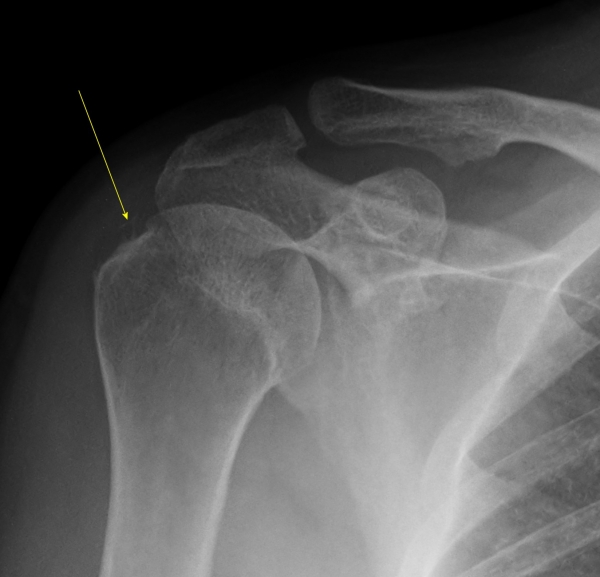

¹æ»ç¼± °Ë»ç :  1Â÷ ¹æ»ç¼± °Ë»ç¿¡¼­ ±Ø»ó°Ç³» °íÀ½¿µ ¼®È¸°¡ °üÂûµÊ(»çÁø 5).